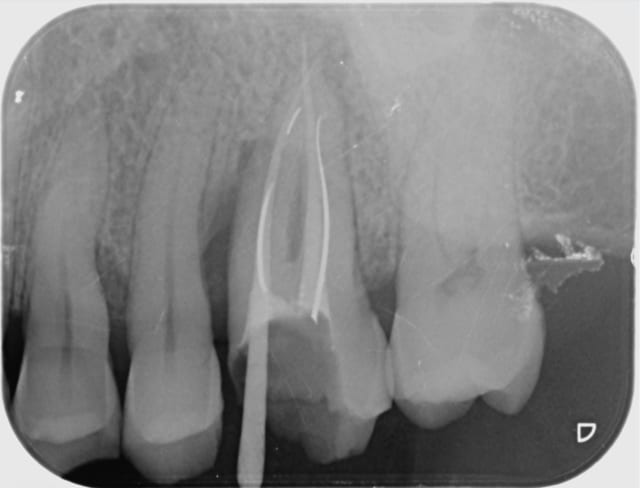

Voici le résultat d'une 3ème séance de recherche du MV 2 le vague à l'âme expliquant l'absence de digue , et mv 2 que j'aurai nommé le CCE pour casse couille endodontique mais n'étant pas endo exclusif je reste courtois avec cette désespérance souvent absente radiologiquement après obturation et dont le trajet incertain me laisse rêveur , quand à la guérison de l'image en mésial prions pour que Saint NaOCl et Saint EDTA veillent sur nous .

Bref cônes d'argent présents MV1 et DV , palatin ?!?!? : aucune image radio , à tout les coups mon MV 2 sera insuffisant et je serai le maillon faible ...)))

Tu remarqueras qu'il n'y a aucune image apicale face aux cônes d'Ag .

Egalement les rapports curieux entre mv1 et mv2 , je suis arrivé à virer le 1/3 milieu du cône qui se trouve dans mv1 et je suis au bout du mv2 que j'ai pénétré facilement après l'avoir cherché 3 séances...